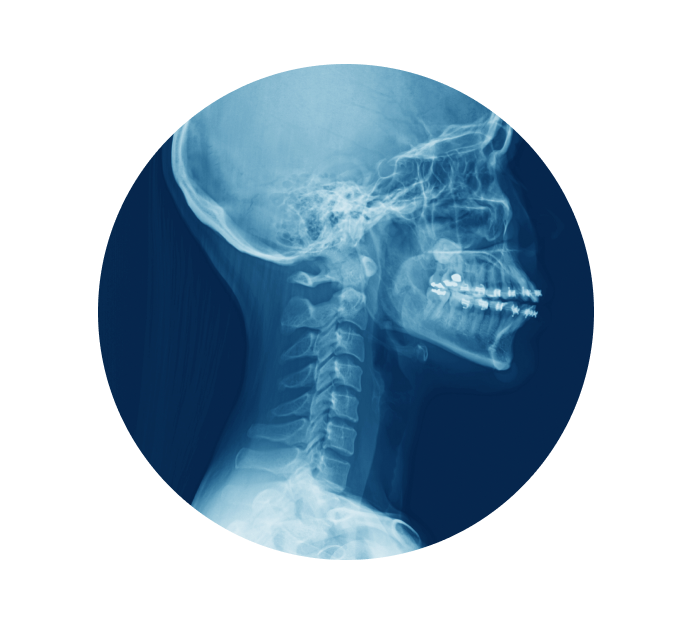

Рентген шейного отдела позвоночника в Казани

Рентген шейного отдела позвоночника позволят выявить такие нарушения и заболевания как остеохондроз, показывает деформацию шейных позвонков, смещение дисков, растяжение, ушиб и не только. При патологиях костных структур этой области тела нарушается ее подвижность, появляются головные боли, нарушается работа вестибулярного аппарата.